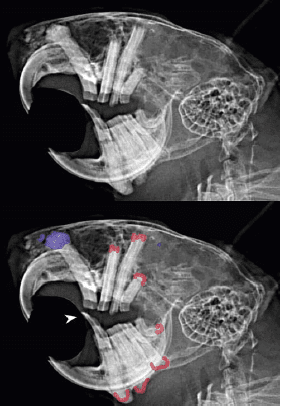

Radiographies latérales obliques Lt 10 V – Rt D du crâne d’un degu présentant une malocclusion des incisives (incisives mandibulaires surlignées en jaune), une élongation apicale des incisives mandibulaires et prémolaires et molaires (apices surlignées en rouge). Dans ce cas, les problèmes respiratoires étaient associés à une masse radio dense correspondant à un élodontome (bleu), qui obstruait la cavité nasale. (Vladimir Jek)